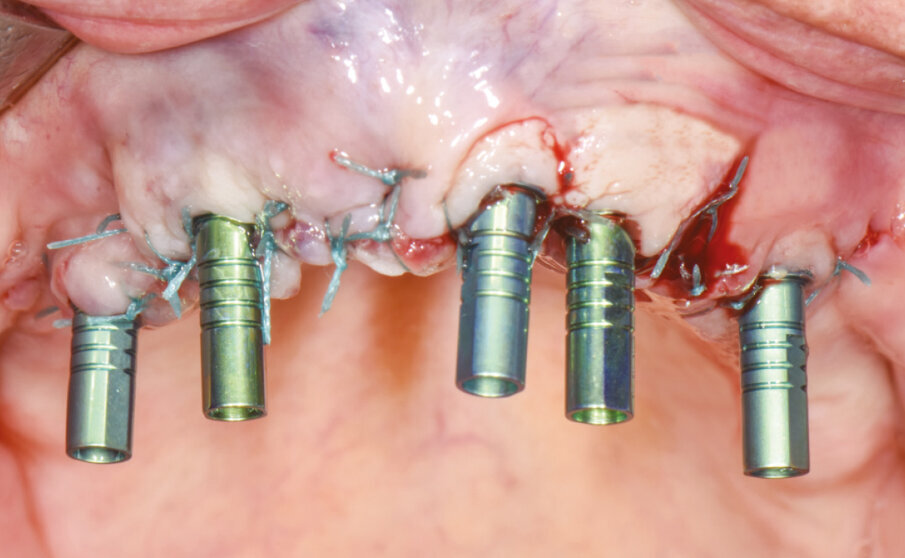

Dopo aver completato la chirurgia con le estrazioni, il posizionamento di cinque impianti (due Max Stability Ø 3,75 mm nelle posizioni 21 e 22 e tre Narrow Ø 2,9 mm nelle posizioni 15, 13 e 25) e la ricostruzione ossea, si esegue una sutura sintetica non riassorbibile.

Si scelgono quindi i monconi MUA con i GH e gli angoli di compensazione adeguati per il raggiungimento del miglior parallelismo. Il posizionamento dei MUA viene eseguito con l’ausilio di viti polifunzionali che permettono di visionare e confermare il parallelismo di emergenza. Dopo aver stabilito la posizione, i MUA vengono battuti con un percussore con punta in PEEK secondo l’asse implantare, attivando così la connessione cono Morse. Successivamente si avvitano i cilindri da incollaggio sui coni dei MUA (Fig. 5).

Fig. 5 - Cilindri da incollaggio posizionati sopra i monconi MUA già definitivamente fissati negli impianti.